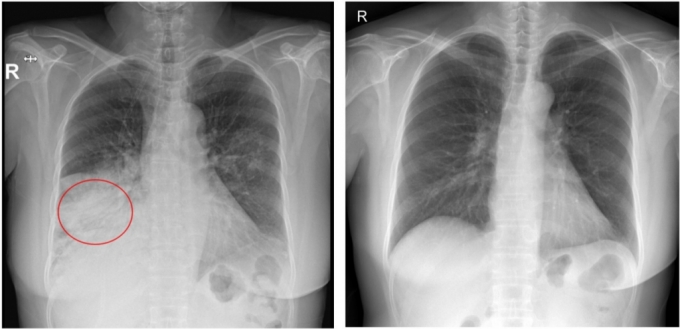

폐렴은 2024년 기준 국내 사망원인 3위이자 호흡계통 질환 사망원인 1위를 기록할 정도로 치명적인 질환이다. 특히 국내 폐렴 환자는 2021년 51만 명에서 2024년 188만명으로 약 3.7배 증가하며 빠르게 확산하는 추세를 보인다.

이처럼 기저질환자에게 폐렴이 치명적인 만큼, 폐렴은 치료보다 예방이 더 중요한 질환으로 꼽힌다. 특히 성인 세균성 폐렴의 가장 큰 원인균인 '폐렴구균'을 막으려면 백신 접종이 가장 효과적이다. 현재 우리나라는 국가예방접종사업(NIP)으로 성인에게 폐렴구균 다당질백신을 접종하지만, 성인에서 폐렴구균으로 인한 폐렴은 꾸준히 늘고 있다.